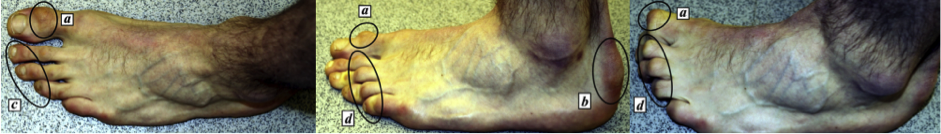

Este tipo de calzado cambia de manera importante la biomecánica del pie, llevando los dedos a una flexión pronunciada, aumentando el arco plantar (Fig. 2), el talón tiende a ir hacia dentro y la pierna gira externamente (Fig. 3), lo que no solo provoca tensión en la planta del pie, sino que también sobrecarga la musculatura de tobillo y dedos, teniendo consecuencias como rigidez y debilidad muscular en el mediano y largo plazo, pudiendo presentar problemas incluso en la vida diaria, como dolor e incomodidad al caminar.

Figura 3. Cambio biomecánica del pie y tobillo y cómo afecta la pierna.

Es por esto que es común la formación de callosidades o ampollas en el dorso de los dedos (Fig. 4), la presencia de dolor o rigidez en la planta del pie, calambres, diferentes tipos de lesiones en las uñas e incluso al largo plazo se puede provocar la desviación del primer ortejo del pie (dedo gordo), lo que se conoce como hallux valgus o “juanete” (Fig. 5). Además, en casos extremos, debido a la gran compresión que puede generar el calzado en caso de ser muy pequeños, podría generar daño a nivel de los nervios del pie, generando adormecimiento, dolor y debilidad.

Figura 4. Formación de callosidades y ampollas en diferentes partes de los dedos y pie.